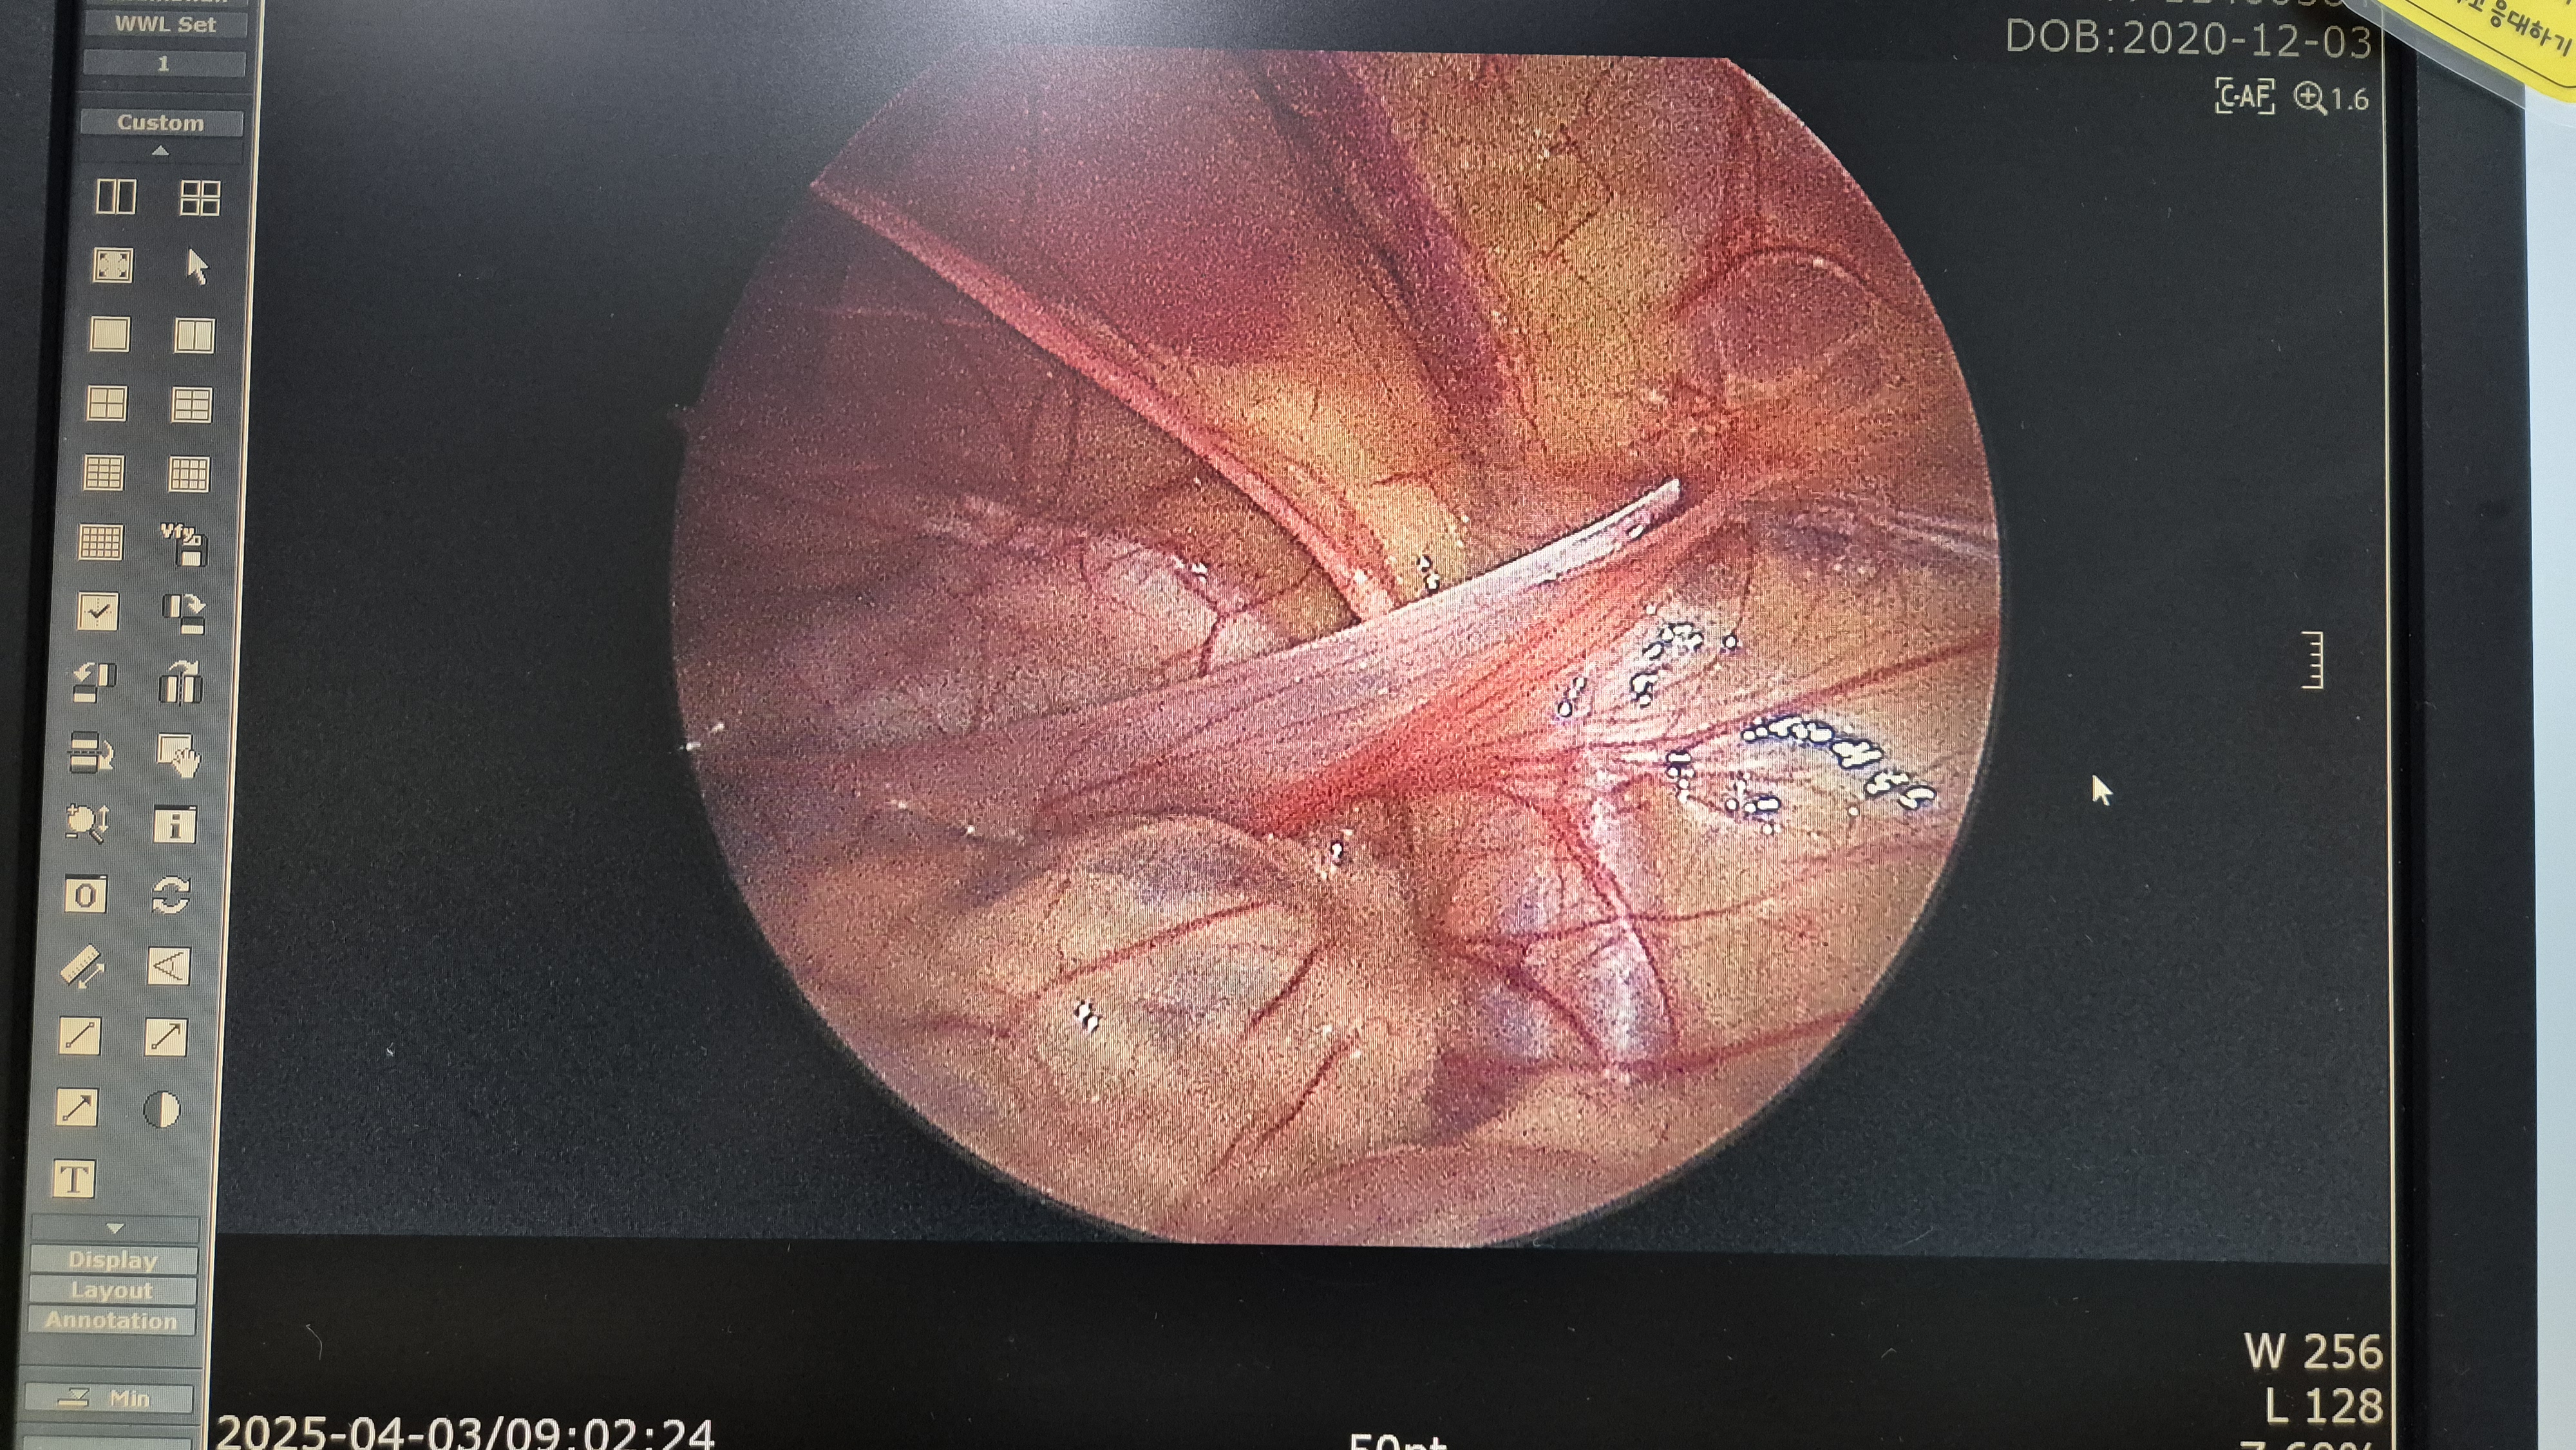

우측 서혜부 탈장.

교정중.